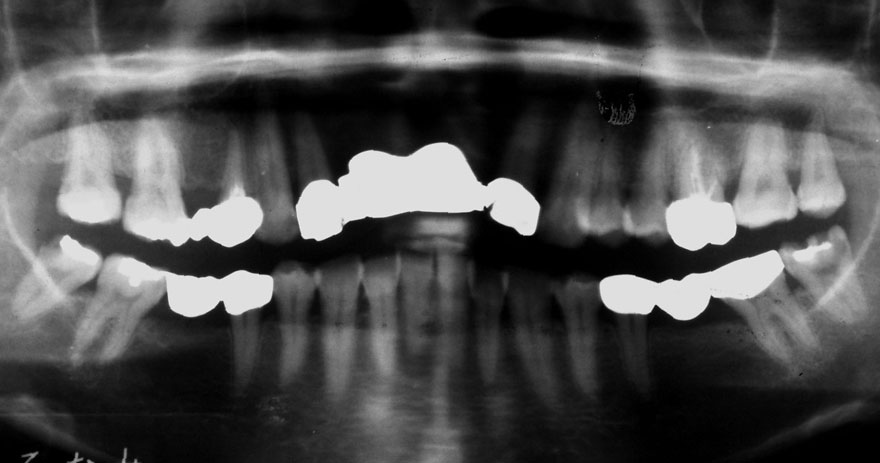

初診時 42歳 男性 平均歯槽骨喪失量:5.30mm

22年後 64歳

平均歯槽骨喪失量:5.554mm

22年間喪失量:-0.24mm

年間喪失速度:-0.01mm

(ケア頻度:1.07ヵ月ごと)